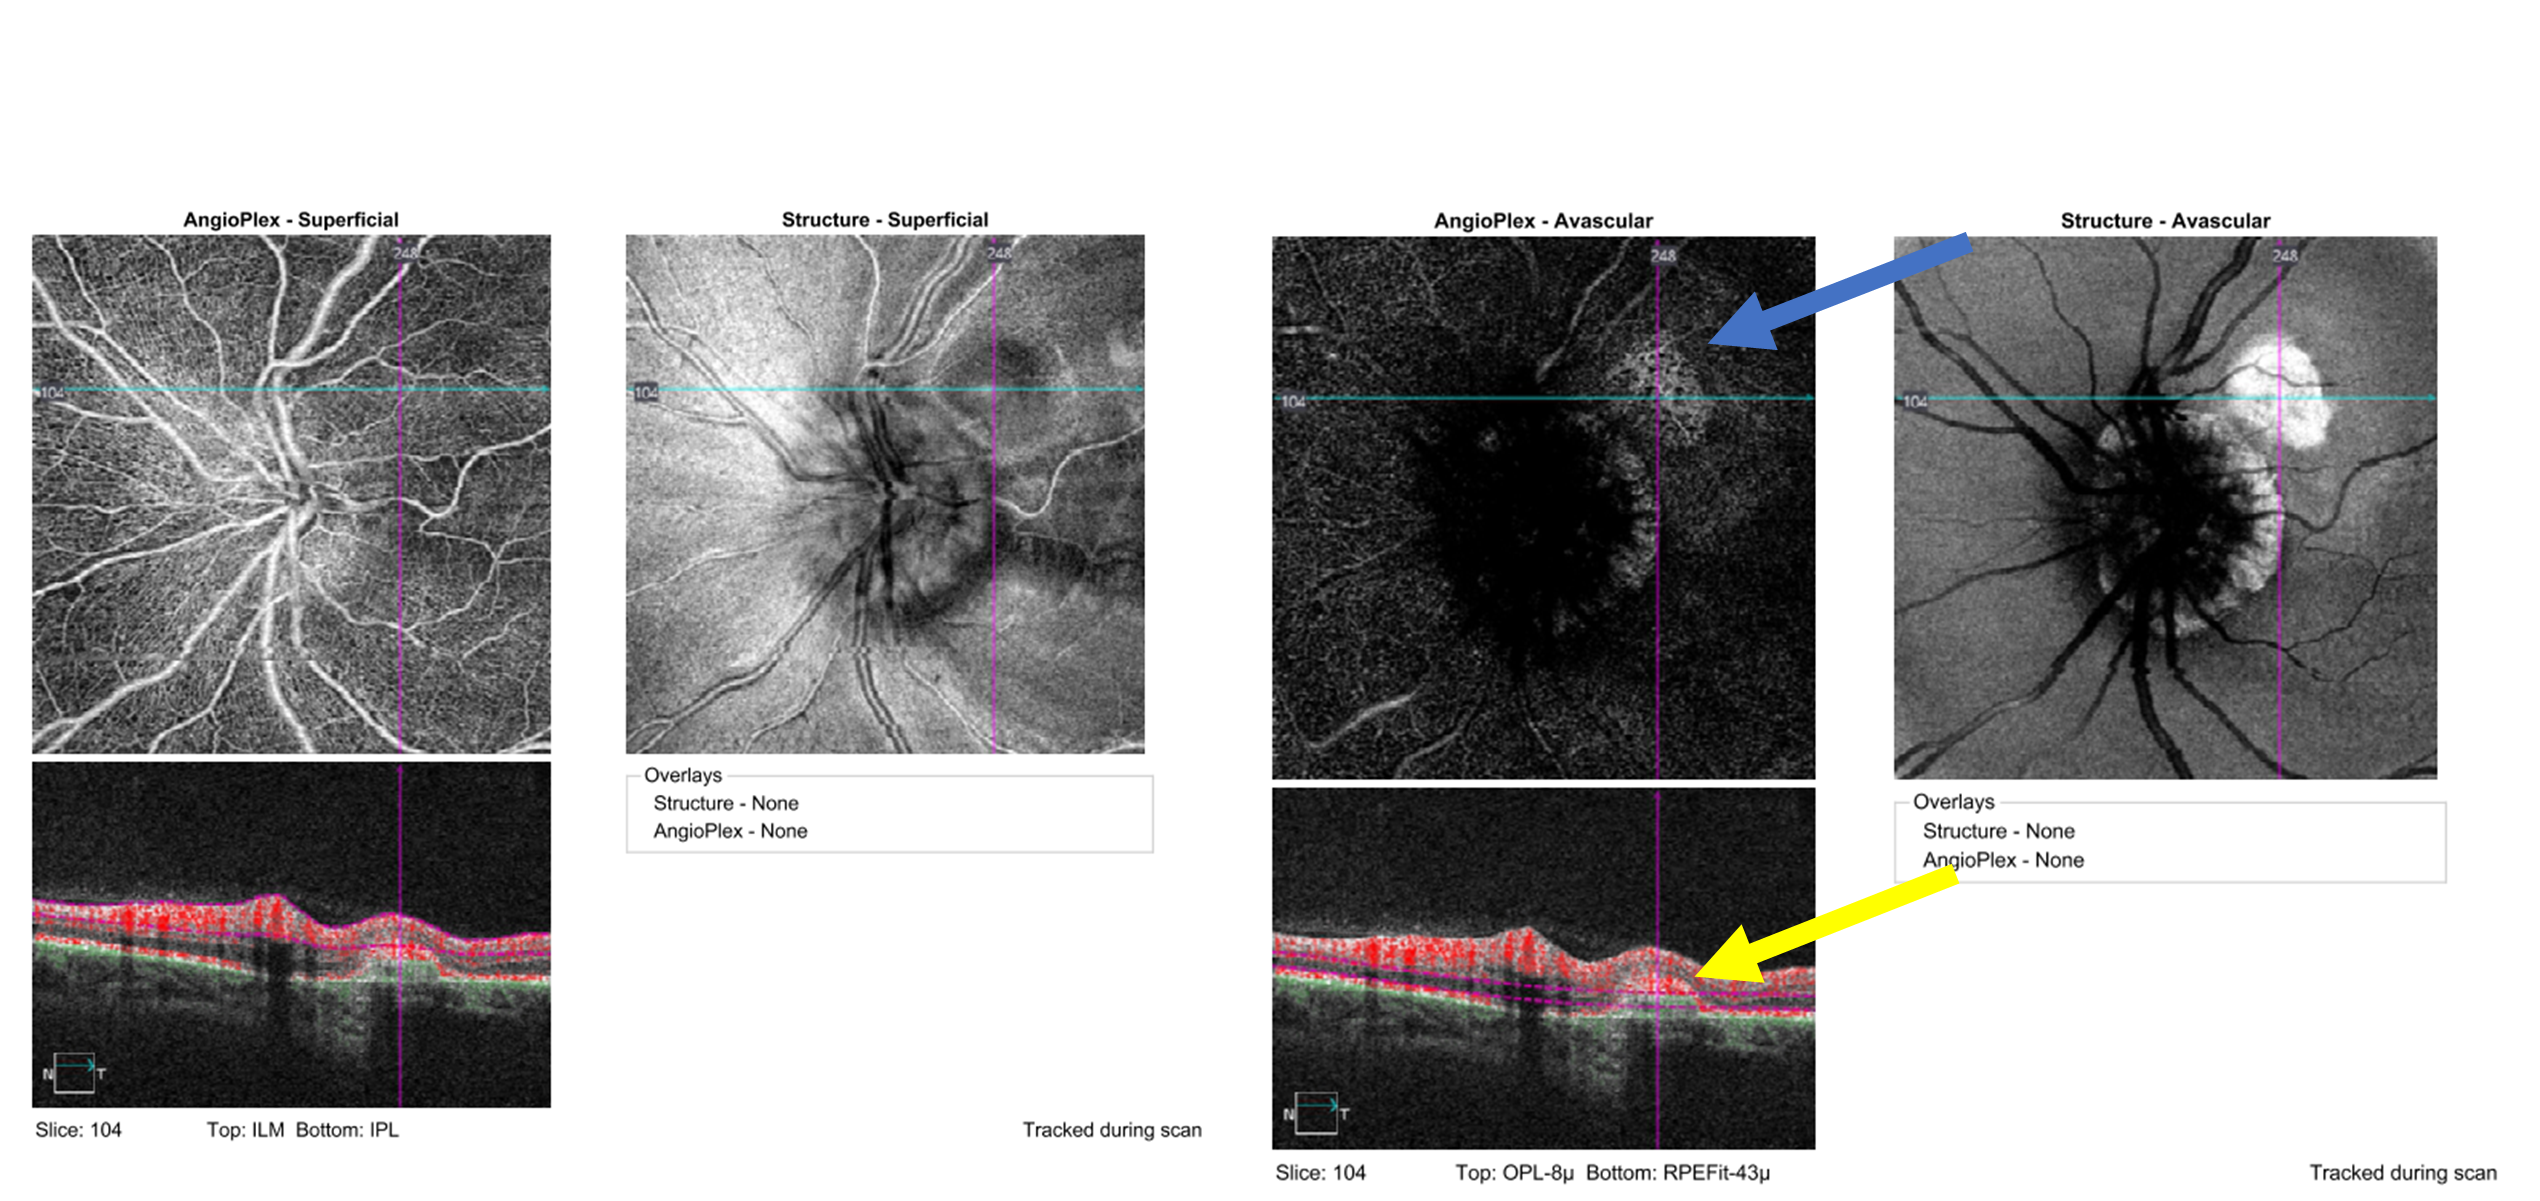

The patient was referred, non-urgently, to a retinal specialist for further evaluation of the presumed inactive CNVM as well as possible prophylactic treatment for the retinal hole. The patient was seen 2 weeks later by the retinal specialist. He opted not to perform fluorescein angiography (FA) and chose OCT angiography (OCT-A) instead. OCT-A scanning was performed and was deemed reliable with no apparent artifacts. Testing showed a net of blood vessels in the avascular zone without flow indicating an inactive CNVM. The retinal specialist also deemed it inactive based on a lack of adjacent fluid and hemorrhaging and due to the surrounding retinal pigment hyperplasia (Figure 10). Barricade laser was performed around the operculated retinal hole. The patient continues to be monitored every 6 months for possible progression of RNFL thinning and visual field defects. Her most recent visit revealed stable findings.

![]() Figure 10. Optical coherence tomography angiography of the left optic nerve and retina, specifically the superficial enface (left) and the avascular enface (right). A hyper-reflective net representative of a choroidal neovascular membrane is present in the avascular layer (blue arrow). No blood flow is noted in the membrane indicating scarring and inactivity (yellow arrow). Click to enlarge |